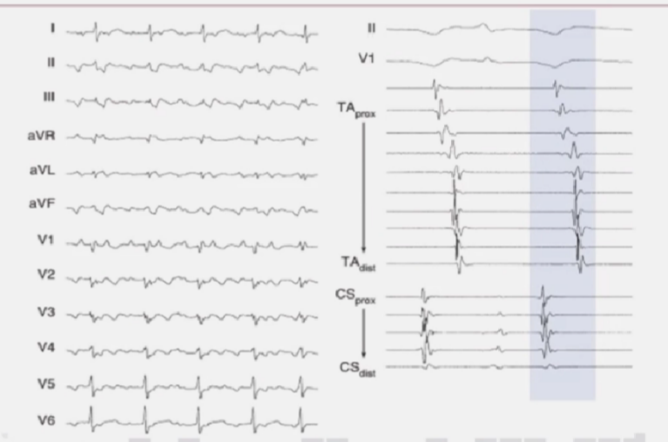

大折返性房速

体表心电图P波等电位线不清楚。围绕三尖瓣环的Halo导管和冠状实导管记录了双侧心房的心内激动,总的心房激动时间接近心动过速周长的90%。

局灶性房速

体表心电图P波等电位线相对清楚。围绕三尖瓣环的Halo导管和冠状导管记录了双侧心房的心内激动,总的心房激动时间小于心动过速周长的50%。